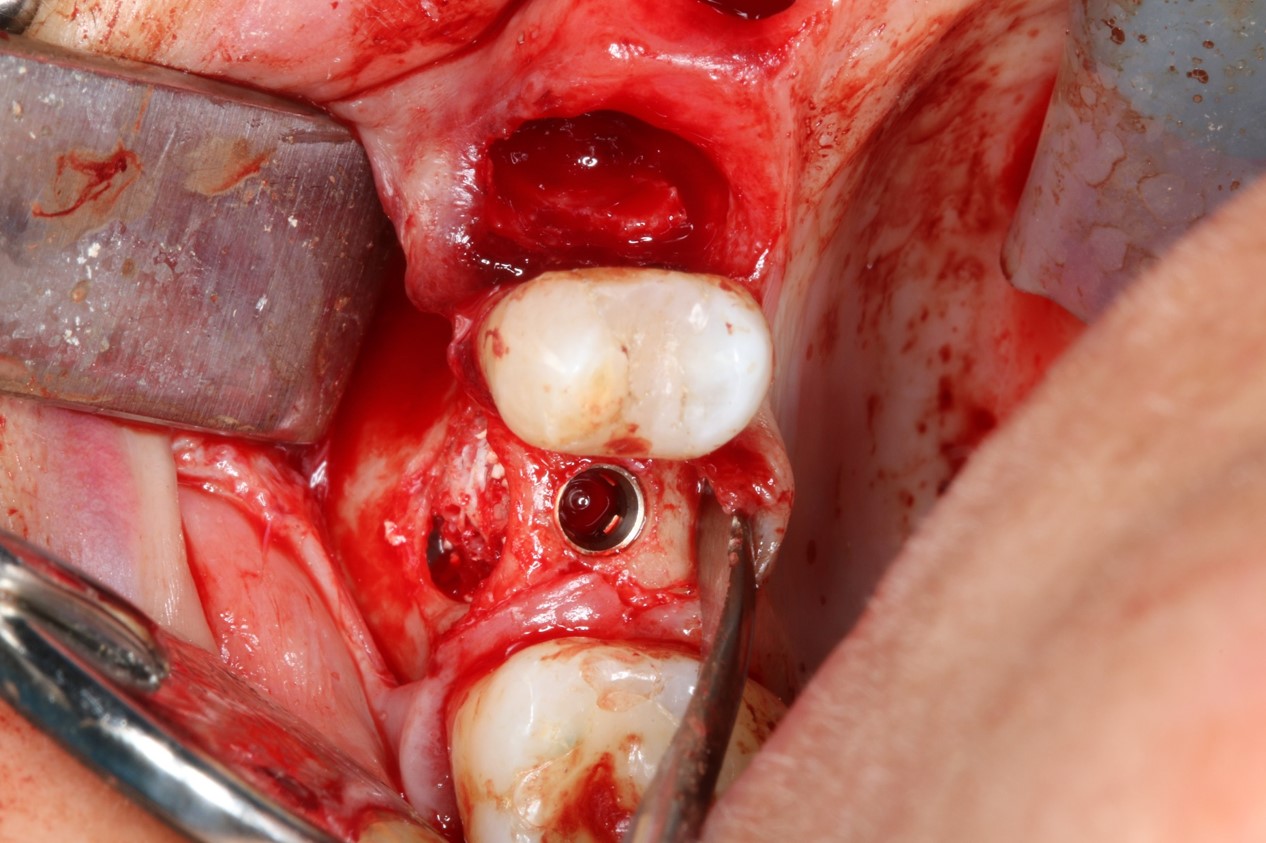

Severe periimplantitis at tooth 15 with bone loss up to 1/3 of the implant